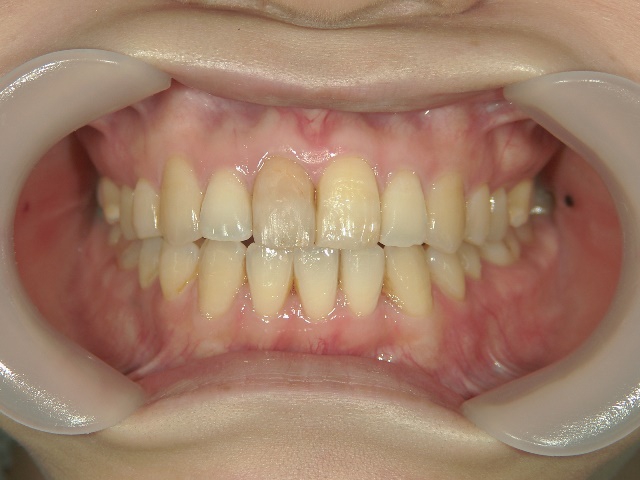

矯正歯科 治療後矯正歯科 プチワイヤー矯正 治療後矯正歯科(プチワイヤー矯正)治療後

矯正歯科 治療後  スペース確保の為、 2番抜歯

矯正_灰色.pngno.37_7548_治療後_上.JPG矯正_灰色.png

no.37_7548_治療後_右.JPGno.37_7548_治療後_正面.JPGno.37_7548_治療後_左.JPG